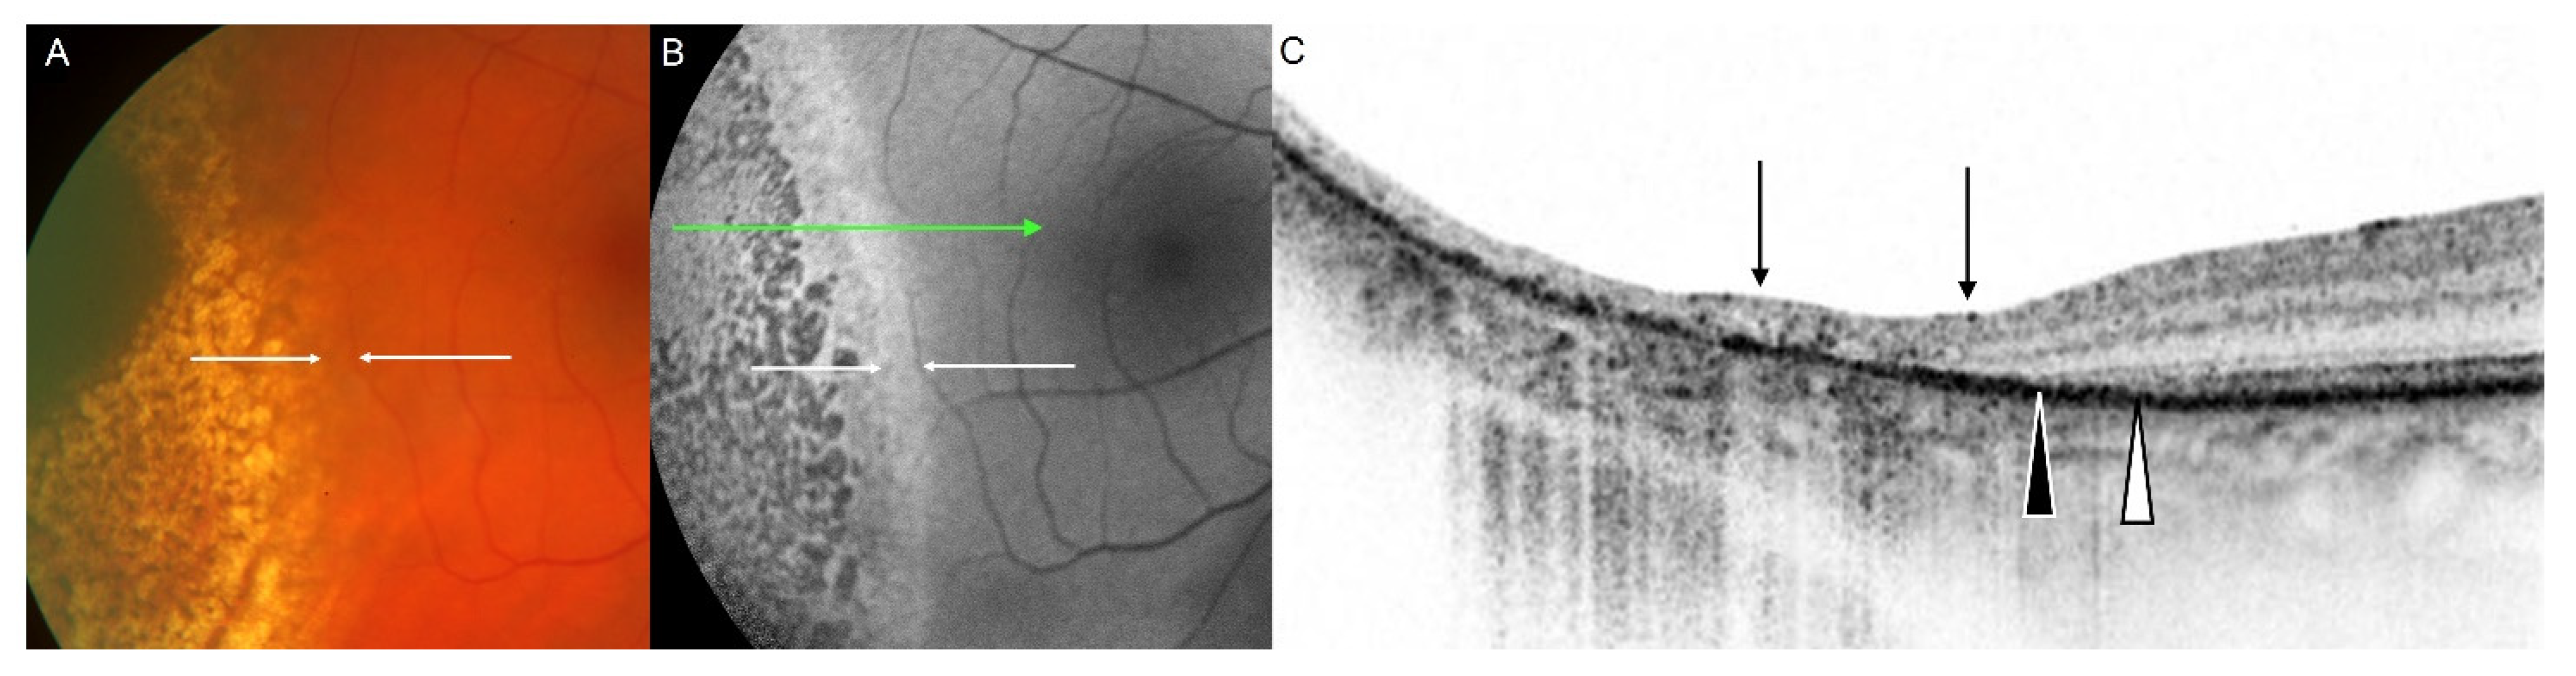

- Materin, M.A.; Raducu, R.; Bianciotto, C.; Shields, C.L. Fundus autofluorescence and optical coherence tomography findings in choroidal melanocytic lesions. Middle East Afr. J. Ophthalmol. 2010, 17, 201–206. [Google Scholar] [CrossRef]

- Samuelsson, D.; Sznage, M.; Engelsberg, K.; Wittström, E. Clinical, optical coherence tomography, and fundus autofluorescence findings in patients with intraocular tumors. Clin. Ophthalmol. 2016, 10, 1953–1964. [Google Scholar] [CrossRef] [PubMed][Green Version]